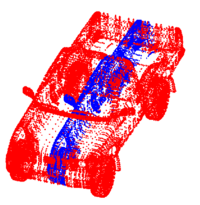

Constrained Registration for Adaptive RadiotherapyA hierarchical approach is described to register two CT scans from different patients. The registration process extracts point clouds representing anatomical structures and aligns them sequentially. The proposed method for registering point clouds can incorporate a variety of constraints including restriction on the injectivity of the deformation field and stationarity of selected landmarks. More... New: I. Kolesov, J. Lee, P.Vela, G. Sharp and A. Tannenbaum. Diffeomorphic Point Set Registration with Landmark Constraints. In Preparation for PAMI.